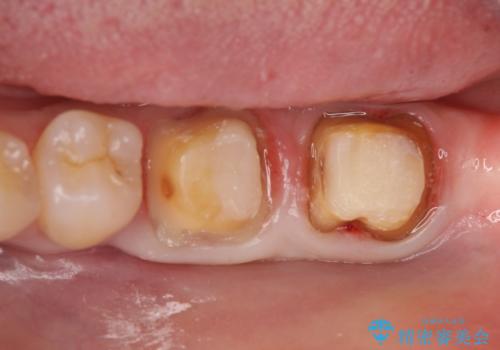

また左下6は遠心にあった歯茎より深い虫歯(縁下カリエス)の問題を解決するため、歯茎を下げる歯周外科手術を行いました。

虫歯が進み歯茎より深くなってしまうと、虫歯を取り残してしまうリスク、樹脂の硬化の妨げ、補綴物の不適合、歯肉炎・歯周病のリスクの増大等様々な弊害が起こり得ます。

そのため当院では歯周外科手術(歯茎を下げる手術)や歯の挺出による、虫歯が歯茎より深いという問題の解決を推奨しております。